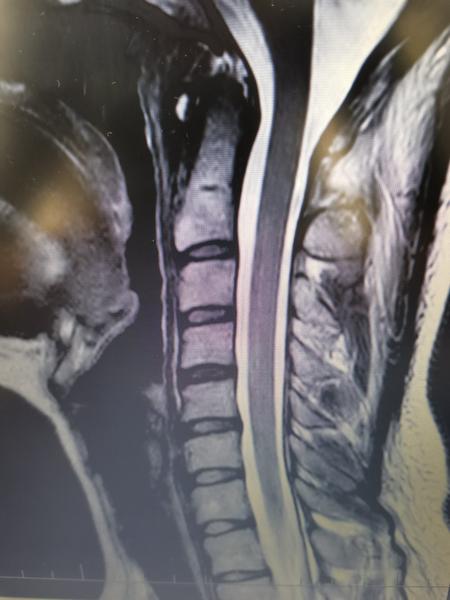

Dáš sem 2 snímky z MRI a niekto ti má povedať diagnózu.🤣 Vidno iba, že máš blokové postavenie/napriamenú krčnú lordózu a disk c4/5 keď tak diskrétne vypukly (bulging) ale to je neškodné... ale na to máš svojho lekára, ktorý ťa na to MRI poslal, aby ti potom aj vysledky povedal...

ja tam tiez nic vazne nevidim